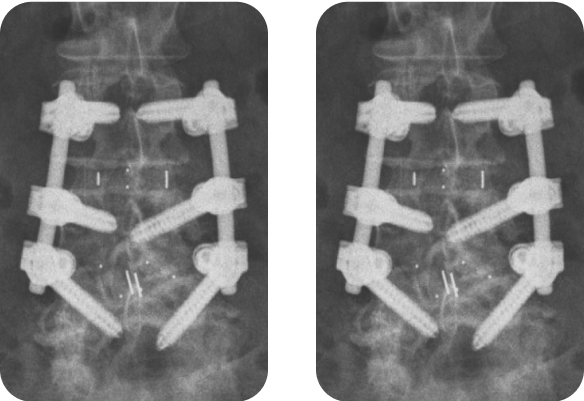

Мужчина, 70 лет, дегенеративный поясничный сколиоз L2-L5 с многоуровневым стенозом позвоночного канала. Выполнен передне-задний спондилодез L2-L5 с помощью кейджей Pezo-A и транспедикулярной системы TangoRS.